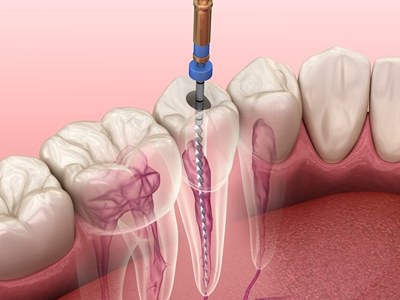

You can rely on us for dependable, comfortable, and expert dental care. With advanced technology, experienced specialists, and personalized treatment plans, we ensure every patient receives trusted, effective solutions for long-term oral health and confident smiles.

He is really a humble person and well-qualified in his profession. My experience was amazing. He explained the issue and solutions and also gave me sometime to think on the procedure. I underwent the implant procedure, which was remarkably pain free. After 3 months the teeth was placed . Thanks to his precise digital measurements and meticulous attention in detail . Today , I have a prefect crown in place . I am grateful to Dr Nitesh Rai for his exceptional skill and compassion , for restoring not just my smile but my confidence too.